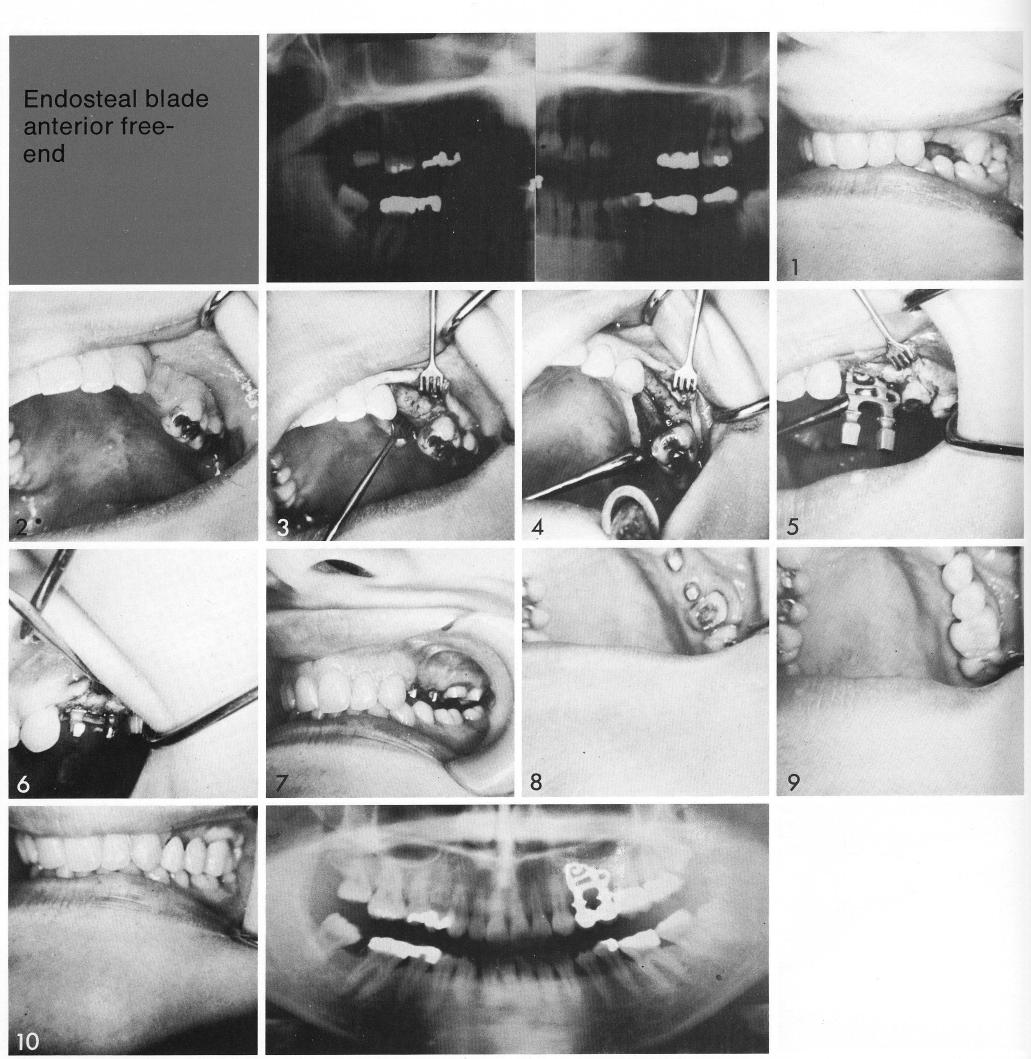

Endosteal blade anterior free-end

The young patient had handsome teeth with a large gap, from which were missing both bicuspids (1,2). The ex-posed ridge (3) was wide, which is not unusual in a young patient with well tended teeth, and served as a generous site for the insertion of a sinus-circumventing, double-posted bladevent (4-6). When the site healed (7,8), the molars were prepared for inclusion in a four-unit restoration. The bladevent allowed near natural dentition (9,10) posteriorly without sacrificing the crowns of more anterior teeth to anchor a conventional fixed restoration.

1 Maxillary double posted bladevent implant inserted in a large gap area